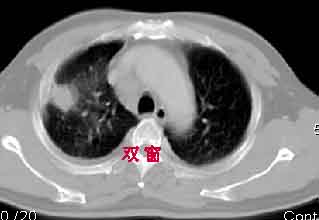

一. 1)症状有无发热及慢性过程.2)化验室检查?3)有无tb接触史?二.右肺上叶见片团状影,边界欠清,外侧方见一结节状软组织影,密度欠均匀,内可见低密度坏死区.周围强化明显,肺内见纤维索条影,局部胸膜增厚,但无明确胸膜凹陷.上叶支气管壁增厚,肺门及纵隔淋巴结增大.右侧胸腔少量积液.诊断意见:1右肺上叶慢性感染性疾病(肺tb?)伴肺门,纵隔淋巴结大.右胸少量积液.右肺上叶结节影多为tb球?2右肺上叶周围型肺ca伴肺门,纵隔淋巴结转移待排.右肺上叶炎变(肺门及纵隔淋巴结压迫).右胸少量积液.等待随返结果.

该病例我的诊断意见:右肺上叶周围型肺癌伴纵隔和右肺门淋巴结增大和右肺上叶阻塞性肺炎{病灶周围致密影以近肺门侧明显!}。右侧少量胸腔积液。